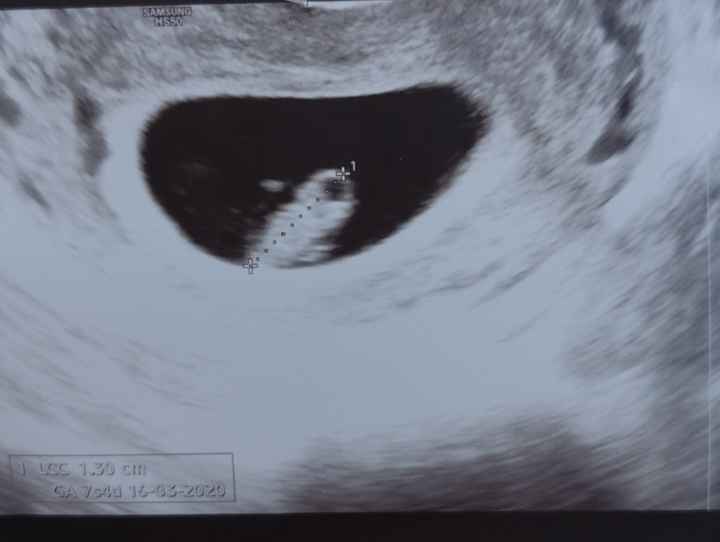

Metodo Ramzi pareri 7ragazze buonasera sono nuova leggendo ho scoperto che qualcuno di voi si intende di questo grazioso metodo ramzi chi di voi saprebbe dirmi se il mio sarà un bimbo o una bimba grazie ragazze siete troppo carine

Per me è un maschio, sempre che abbia visto bene il cordone! 👵🏻

Sembra un maschietto Smiley love anche se, come dice Alessia, non si vede benissimo!!

Secondo me è maschietto...somiglia alla mia primissima ecografia..

Sembrerebbe maschietto 😊 ma non vedo dov è attaccato il cordone